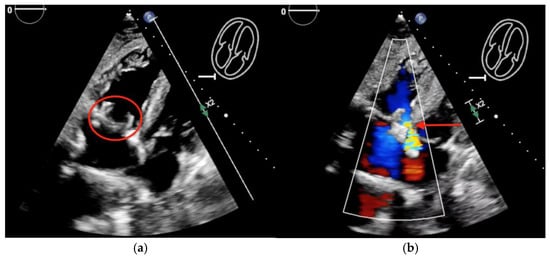

The purpuric rash was clinically consistent with leukocytoclastic vasculitis per dermatologic consultation, although a skin biopsy was not performed. A transthoracic echocardiogram showed normal ejection fraction, but revealed a large tricuspid valve (TV) vegetation (Video S1). A transesophageal echocardiogram confirmed large, multilobed vegetations on the TV measuring 1.9 cm × 0.9 cm on the anterior leaflet and 2.2 cm × 0.7 cm on the posterior leaflet associated with severe tricuspid regurgitation (Figure 2, Videos S2 and S3). (For a video of the transesophageal echocardiogram with cardiologist commentary, see Video S4.)

Figure 2. Transesophageal echocardiogram showing: (a) large, multi-lobed tricuspid valve vegetations associated with valve perforation and (b) severe tricuspid valve regurgitation (white arrow).